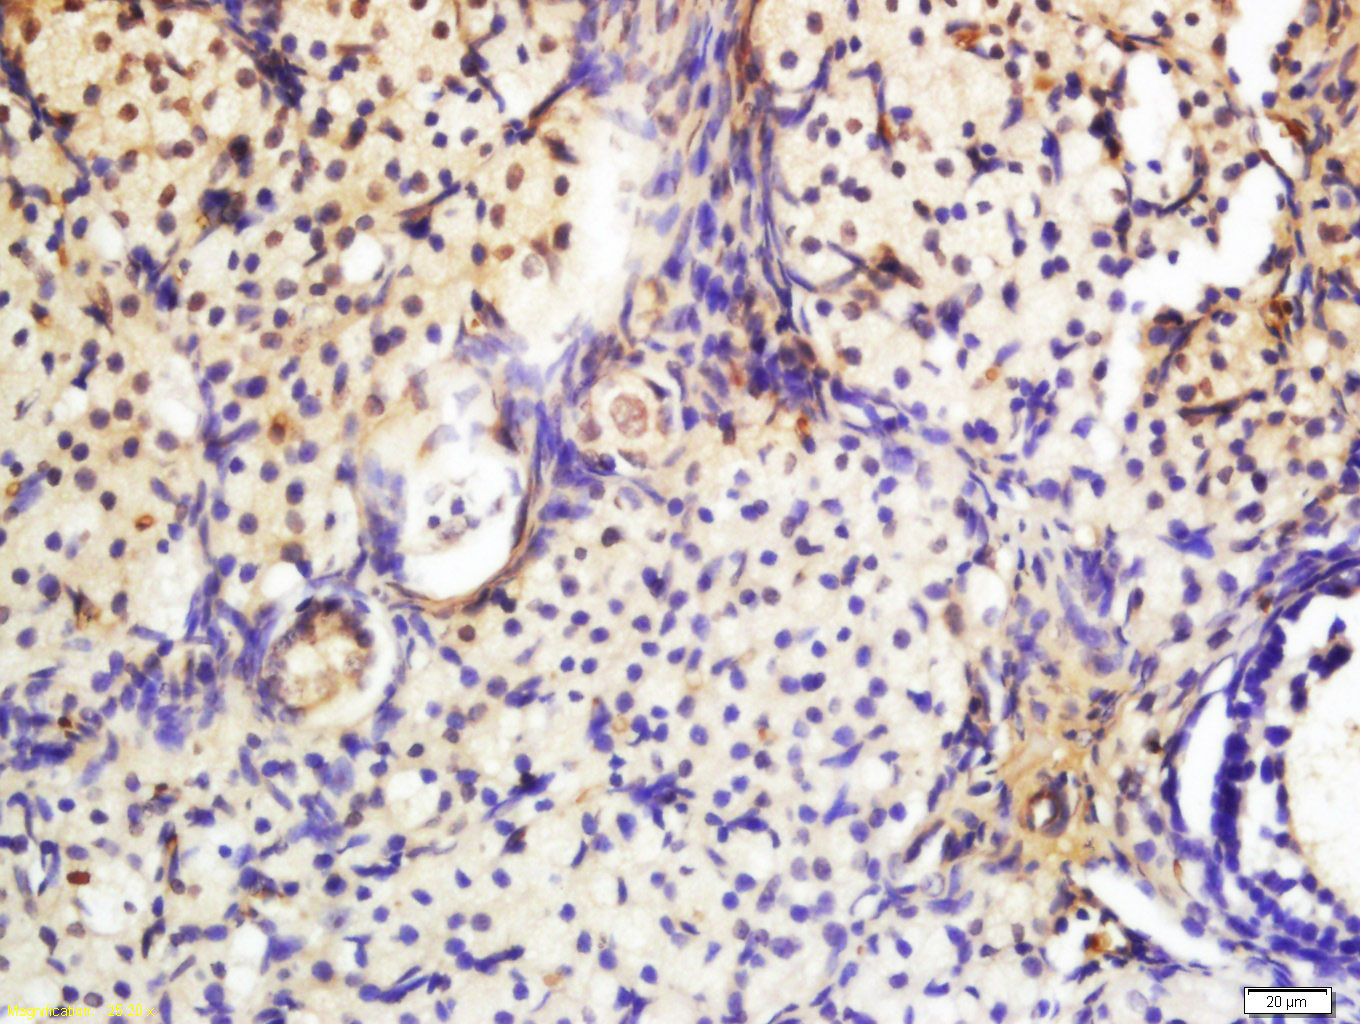

Tissue/cell: mouse ovary tissue; 4% Paraformaldehyde-fixed and paraffin-embedded; Antigen retrieval: citrate buffer ( 0.01M, pH 6.0 ), Boiling bathing for 15min; Block endogenous peroxidase by 3% Hydrogen peroxide for 30min; Blocking buffer (normal goat serum,C-0005) at 37℃ for 20 min; Incubation: Anti-Phospho-PAK2 (Ser20) Polyclonal Antibody, Unconjugated(bs-3317R) 1:200, overnight at 4°C, followed by conjugation to the secondary antibody(SP-0023) and DAB(C-0010) staining